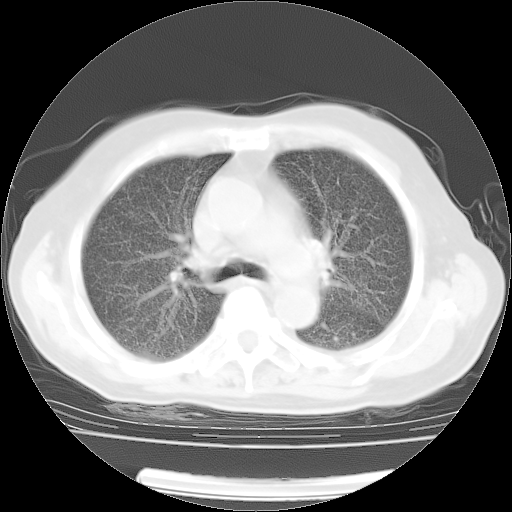

肺部CT平扫未见异常。